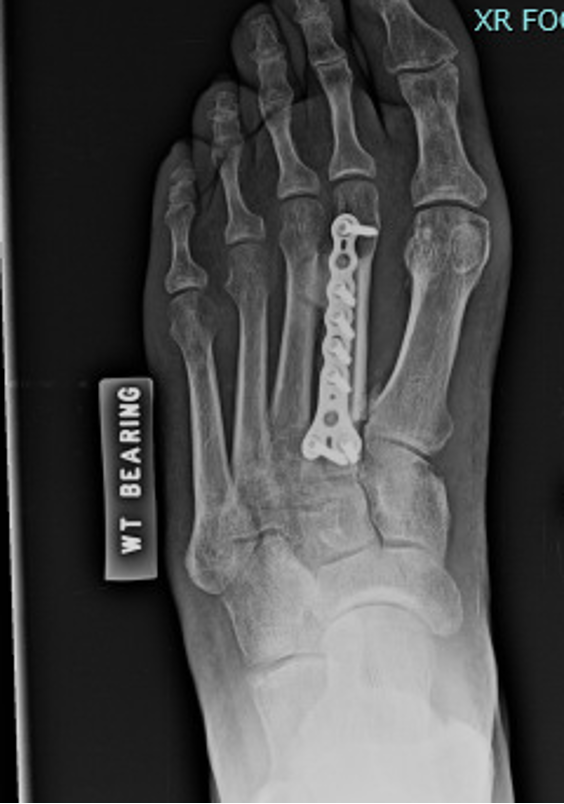

After wound healing, we took the patient back to the operating room to remove the external fixator, place a fibular graft, and to perform open reduction and internal fixation (ORIF) of the second metatarsal. After removing the external fixator, we made a dorsal incision over the second metatarsal, exposing the bone. The second metatarsal was severely comminuted and angled. A sagittal saw then resected an approximately five cm section of the severe comminution and non-viable bone. We measured the deficit in the second metatarsal.

Under fluoroscopy, we then created a longitudinal incision over the central fibula, eight cm proximal to the ankle joint, to help prevent syndesmotic instability. A sagittal saw then helped harvest fibula graft to fit the previously measured deficit. After prepping the distal and proximal aspect of the remaining neck and base of the second metatarsal, the fibular graft was pressed and fitted into the defect. Once confirmed that the graft was the appropriate length to fit the deficit, we brought the graft to the back table, where we fixated a Y-plate to the graft to allow for ease of placement and fixation of the graft to the remaining bone fragments. At seven months postop, the patient ambulated in regular shoe gear with no complaints of foot pain.